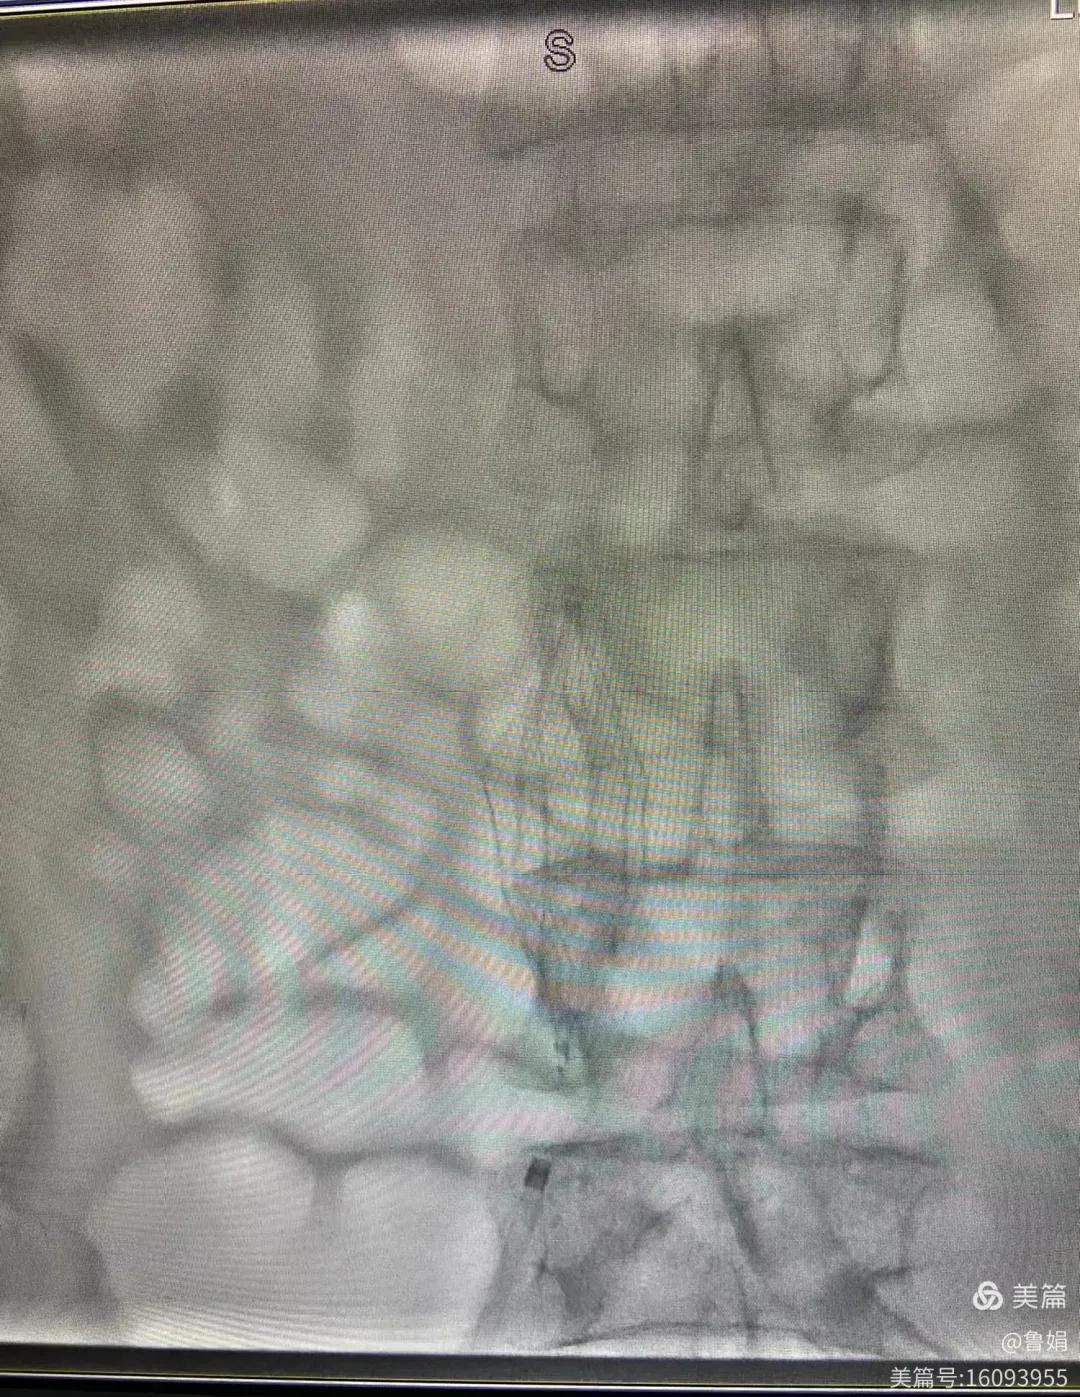

11月3日,漯河市中醫(yī)院血管外科副主任周創(chuàng)業(yè)與腦二科介入醫(yī)生孫亞中,兩位醫(yī)生為一位腦梗死伴下肢深靜脈血栓形成患者成功開展下腔靜脈濾器置入術(shù)。

圖片術(shù)后濾器順利植入

患者女,73歲,于2024年11月16日在外院行右側(cè)大腦中動脈支架植入手術(shù),后轉(zhuǎn)入漯河市中醫(yī)院腦二科繼續(xù)治療,患者來時訴左側(cè)肢體痛,觸之溫覺減退,主管醫(yī)生孫亞中副主任中醫(yī)師,為患者查體可見左下肢輕中度水腫,雙下肢深靜脈彩超檢查示:左下肢深靜脈血栓處于進(jìn)展期。孫亞中考慮患者隨時有血栓脫落、肺栓塞、急性肺梗死風(fēng)險,需急診行下腔靜脈濾器植入,立即請相關(guān)科室聯(lián)合會診,并聯(lián)系血管外科副主任周創(chuàng)業(yè),周創(chuàng)業(yè)副主任得知患者病情危重急忙從家里來到醫(yī)院參與急診手術(shù)。

經(jīng)認(rèn)真查看患者病例,探討患者病情及術(shù)中潛在風(fēng)險因素,多科會診后急診為患者開展介入手術(shù),術(shù)中周創(chuàng)業(yè)副主任、孫亞中副主任中醫(yī)師二人通力合作,手術(shù)順利,病人術(shù)中出血少,生命體征平穩(wěn),現(xiàn)在腦二科病房繼續(xù)對癥治療。(介入中心:魯娟)